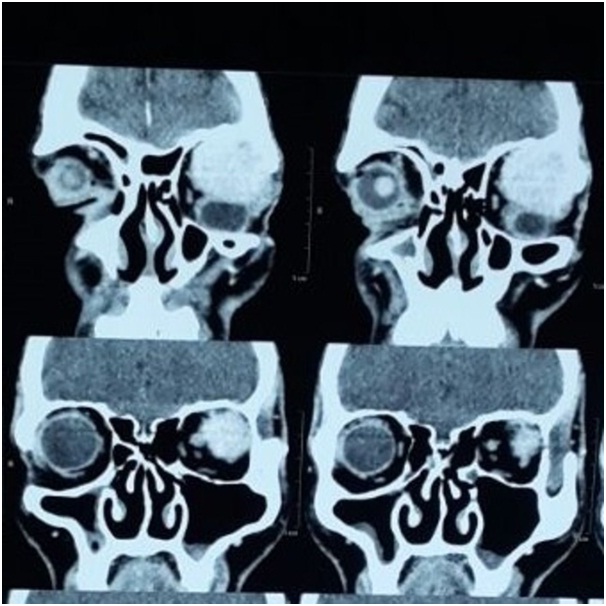

Computed tomography of the left orbit showed a 4.3x3.7x2.8cm sized homogeneous enhancing hyperdense lesion in the superior compartment of the left orbit originating in the extraconal compartment and extending intraconally, causing marked proptosis. The mass was seen distorting the globe and causing scleral buckling, most marked superolaterally [Table/Fig-2,3 and 4]. The fat planes with the optic nerve, sclera, lateral rectus, superior rectus, inferior oblique muscle were focally lost. It showed thinning but no erosion of roof of the left orbit. The differential diagnosis given upon imaging was: lacrimal gland tumour, nerve sheath tumour or atypical cavernous haemangioma.

Coronal view of contrast computed tomography scan showing homogenously enhancing lesion causing inferotemporal displacement of globe with marked distortion of globe.

Sagittal view of contrast computed tomography scan showing homogenous enhancing lesion in extraconal compartment extending intraconally and distorting the globe.